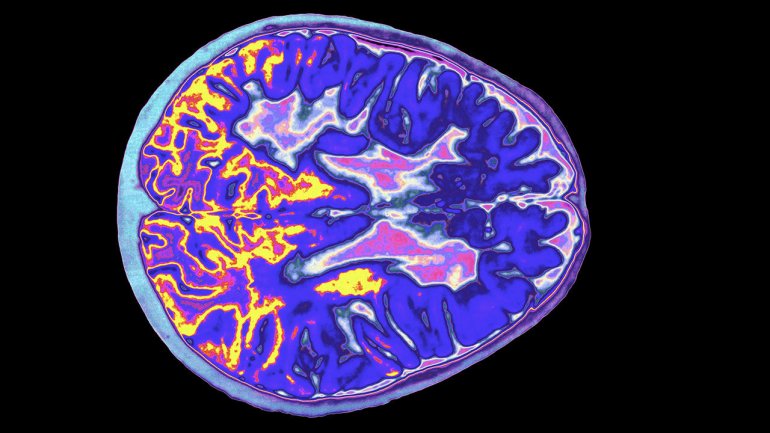

Η έρευνα εξέτασε δεδομένα από 840 Αυστραλούς που συμμετείχαν στην Ausimmune Study για να διαπιστώσει εάν υπήρχε σχέση μεταξύ της μεσογειακής διατροφής που περιλαμβάνει μη επεξεργασμένο κόκκινο κρέας, όπως το αρνί, το βόειο κρέας και το χοιρινό και μειωμένου κινδύνου ενός πρώτου επεισοδίου απομυελίνωσης του Κεντρικού Νευρικού Συστήματος, ενός κοινού προδρόμου της MS.

Είναι ασαφές γιατί η κατανάλωση κόκκινου κρέατος σε συνδυασμό με μια υγιεινή διατροφή μπορεί να μειώσει τον κίνδυνο της MS, αλλά το κόκκινο κρέας περιέχει εκτός από πρωτεΐνες σημαντικά μικροθρεπτικά συστατικά όπως σίδηρο, ψευδάργυρο, σελήνιο, κάλιο, βιταμίνη D και μια σειρά βιταμινών Β, συστατικά που είναι σημαντικά για την υγιή νευρολογική λειτουργία.